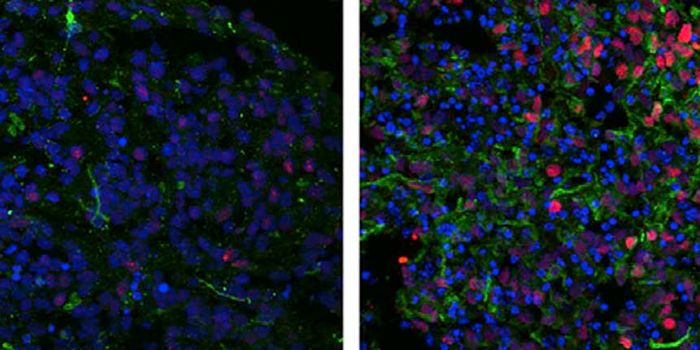

FEB 21, 2023Cell & Molecular BiologyThe Griffith Lab at UNC discovered telomeric protein & potential biomarker VR (green), shown in the nuclei (blue) of hum ...